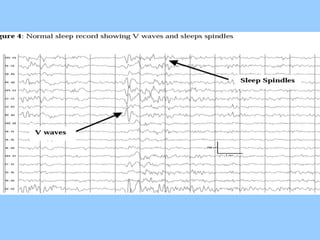

1. The document discusses EEG patterns and findings in various neurological conditions seen in children. It includes descriptions of normal EEG findings as well as abnormal patterns seen in conditions like absence seizures, West syndrome, benign childhood epilepsy with centrotemporal spikes, Lennox-Gastaut syndrome, non-convulsive status epilepticus, subacute sclerosing panencephalitis, and herpes encephalitis.

3. International standards for EEG electrode placement and recording parameters are reviewed. Characteristics of different EEG waves, amplitudes, and patterns are described.